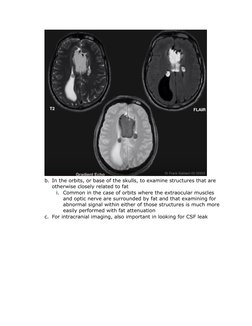

7. Fat suppression + T2

a. Performed as part of a gradient echo sequence where the intention

is not particularly to suppress fat, but to make it more susceptible

to paramagnetic effects

b. In the orbits, or base of the skulls, to examine structures that are

otherwise closely related to fat

i. Common in the case of orbits where the extraocular muscles

and optic nerve are surrounded by fat and that examining for

abnormal signal within either of those structures is much more

easily performed with fat attenuation

c. For intracranial imaging, also important in looking for CSF leak